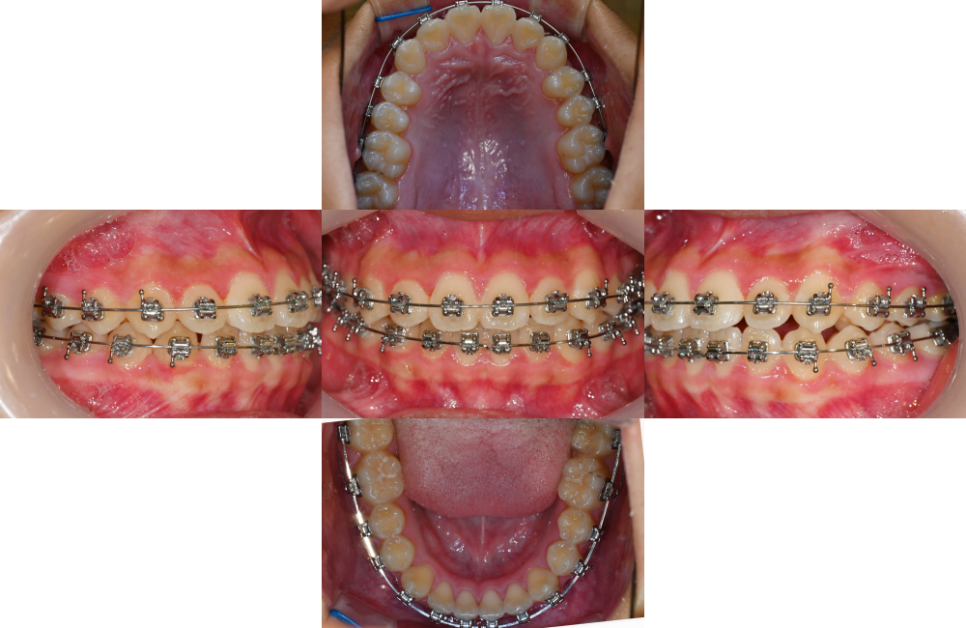

23.08.17

총생은 이가 들어설 공간이 부족해서

이들이 겹치거나 비틀어진 상태를 말하는데요.

많은 분들이

단순히 ‘치아가 삐뚤어졌다’고만

생각하시지만, 실제로는

훨씬 복잡한 문제로,

가장 큰 문제점으로는

위아래 어금니가 제대로 맞물리지 않는

부정교합이 발생한다는 점입니다.

다행히 심한 골격적 문제나 심각한 총생이 아니라면

발치 없이도 치열 개선이 가능합니다.